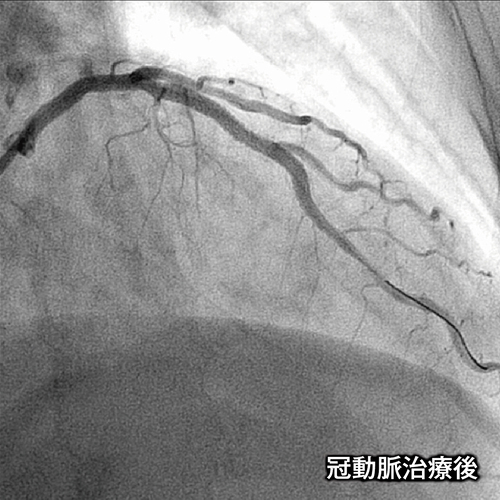

冠動脈治療後の画像

当院では、カテーテルから造影剤を注入し、冠動脈を直接造影する検査(CAG)や、カテーテルを用いて動脈硬化で狭くなった冠動脈を拡張させる経皮的冠動脈形成術(PTCAまたはPCI)などを行っています。